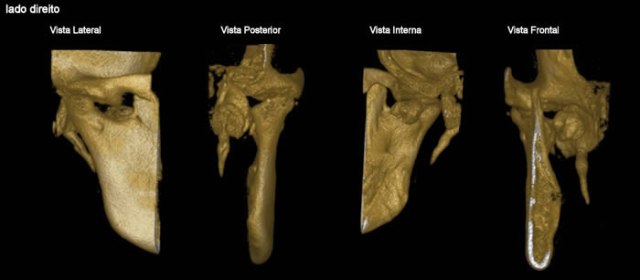

CASO 1 - Anquilose de ATM

Paciente com assimetria, limitação de abertura bucal. Observa-se união óssea da porção posterior e lateral do côndilo ao esfeóide e zigomático.